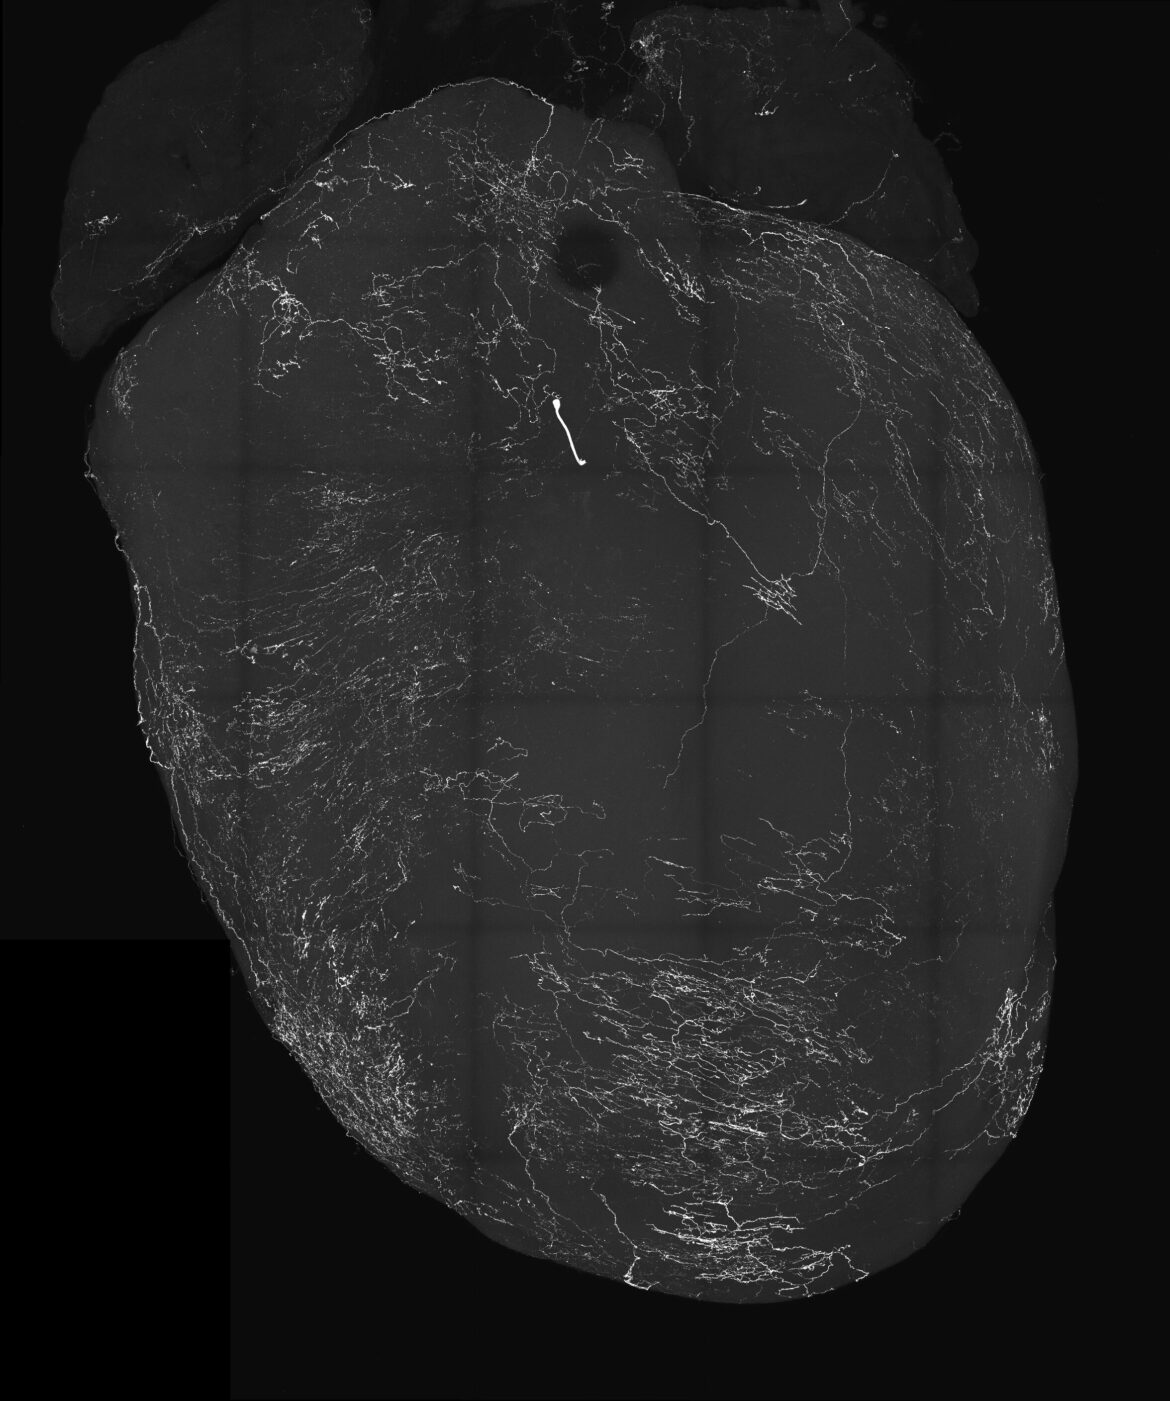

Une image d’un cœur marqué par des neurones sensoriels vagaux. Dans une nouvelle étude publiée dans la revue Nature, des chercheurs de l’UC San Diego et leurs collègues ont découvert que ces neurones déclenchent des évanouissements, jetant ainsi les bases du traitement des troubles liés à l’évanouissement. Crédit : Augustine Lab, UC San Diego

Les chercheurs se sont concentrés sur la génétique derrière un groupe sensoriel connu sous le nom de ganglions noueux, qui font partie des nerfs vagues qui transportent les signaux entre le cerveau et les organes viscéraux, y compris le cœur. Plus précisément, les neurones sensoriels vagaux, ou VSN, projettent des signaux vers le tronc cérébral et seraient associés au BJR et à l’évanouissement. Dans leur recherche d’une nouvelle voie neuronale, ils ont découvert que les VSN exprimant le récepteur Y2 du neuropeptide Y (connu sous le nom de NPY2R) sont étroitement liés aux réponses bien connues du BJR.

En étudiant cette voie chez la souris, les chercheurs ont été surpris de constater que lorsqu’ils déclenchaient de manière proactive les VSN NPY2R à l’aide de l’optogénétique, une méthode de stimulation et de contrôle des neurones, les souris qui se déplaçaient librement s’évanouissaient immédiatement. Au cours de ces épisodes, ils ont enregistré des données provenant de milliers de neurones dans le cerveau des souris, ainsi que l’activité cardiaque et les modifications des traits du visage, notamment le diamètre de la pupille et les fouettements.